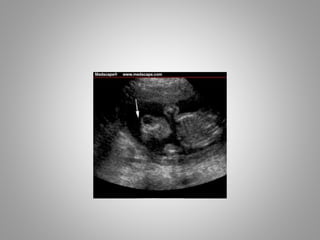

• Head changes in Open Spina Bifida

1. Ventriculomegaly……….........

2. Lemon Sign……………………….

3. Banana Sign………………………

B/L Frontal Bone Indentation

Banana Sign

Normal Cerebellum & CM

Banana shaped Cerebellum with

obliterated CM

• The banana sign and effacement of cisterna

magna are due to fluid leakage allowing

cerebellum to compress into lower posterior

fossa.

• Cerebellum hemispheres wraps around lateral

aspect of brain stem and so asumes C-shape

{Banana Shape} in transcerebellar plane.

• These sonographic findings constitute Chiari II

malformation.

• Head changesin Open Spina Bifida 1. Ventriculomegaly………......... 2. Lemon Sign………………………. 3. Banana Sign………………………

Banana Sign Normal Cerebellum& CM Banana shaped Cerebellum with obliterated CM

• The bananasign and effacement of cisterna magna are due to fluid leakage allowing cerebellum to compress into lower posterior fossa. • Cerebellum hemispheres wraps around lateral aspect of brain stem and so asumes C-shape {Banana Shape} in transcerebellar plane. • These sonographic findings constitute Chiari II malformation.